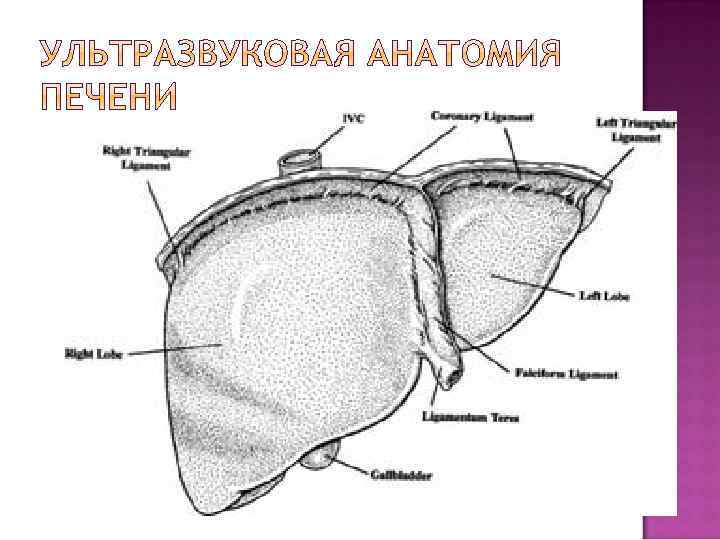

Визуализируется в правом подреберье Исключение инверсия внутренних органов Изображение множества срезов – трехмерная реконструкция в голове исследователя Форма печени при поперечном сканировании (продольном срезе через все доли печени) – в виде большой запятой Различают четыре доли (правая, левая , хвостатая, квадратная) и восемь сегментов

1. 2. 3. 4. Анатомические ориентиры между долями: Ложе желчного пузыря – между правой и квадратной Круглая связка и борозда круглой связки – между квадратной и левой долями Ворота печени – между квадратной и хвостатой долями Выемка венозной связки (удвоенный листок капсулы и клетчатка) – между левой и хвостатой долями